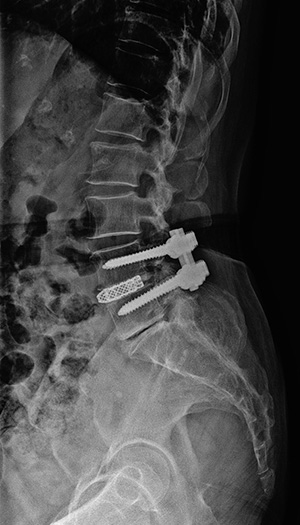

▼ 척추뼈 2개를 묶은 유합술 ▼

• 유합술 전면 X-ray

• 유합술 측면 X-ray

▼ 척추뼈 3개를 묶은 유합술 ▼